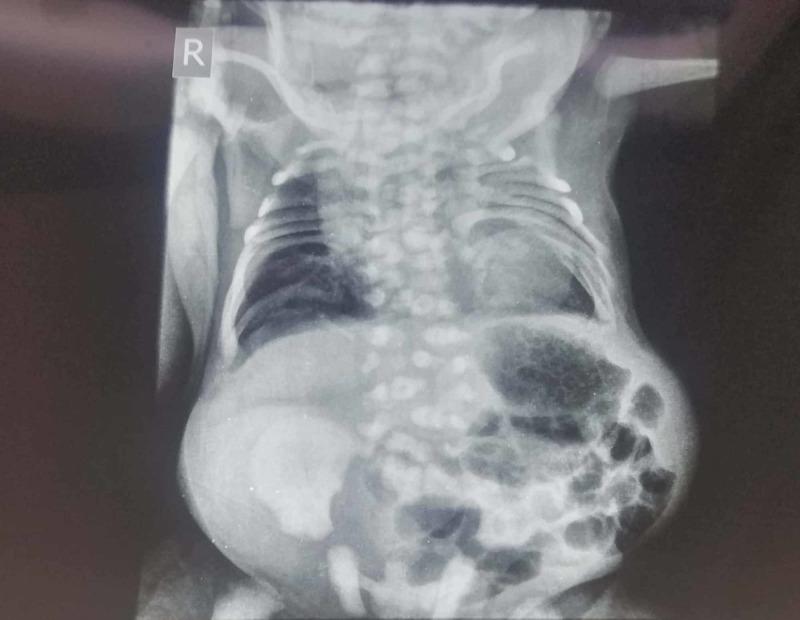

Spondyloepiphysal dysplasia (SED) is an inheritable dysplasia of the bone due to a defect in collagen. It has a prevalence of 3.4 per million. It has two important types, congenita and tarda, which are differentiated by the age presentation and heritage mode. SED congenita can present a significant reduction in the upper segment to a lower segment ratio. Collagen mutation results in abnormal growth and development of spine and limb bones. The complex pattern of craniofacial anomalies is due to defective ossification and connective tissue problem. We here present the case of a three-hour-old girl with a short trunk and craniofacial anomalies that brought in respiratory distress to the neonatal intensive care unit. This condition is rare and thus poses a major diagnostic challenge at an early stage.

脊椎骨骺发育不良(SED)是一种由于胶原蛋白缺陷导致的遗传性骨骼发育不良。其发病率为百万分之3.4。它有两种重要类型,即先天性和迟发性,可通过发病年龄和遗传方式进行区分。先天性SED可表现为上身与下身比例显著降低。胶原蛋白突变导致脊柱和四肢骨骼的异常生长和发育。颅面畸形的复杂模式是由于骨化缺陷和结缔组织问题所致。我们在此报告一例3小时大的女婴病例,该女婴躯干短小且有颅面畸形,因呼吸窘迫被送入新生儿重症监护病房。这种情况很罕见,因此在早期阶段构成了重大的诊断挑战。